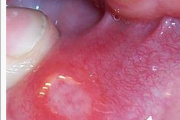

Herpes simplex